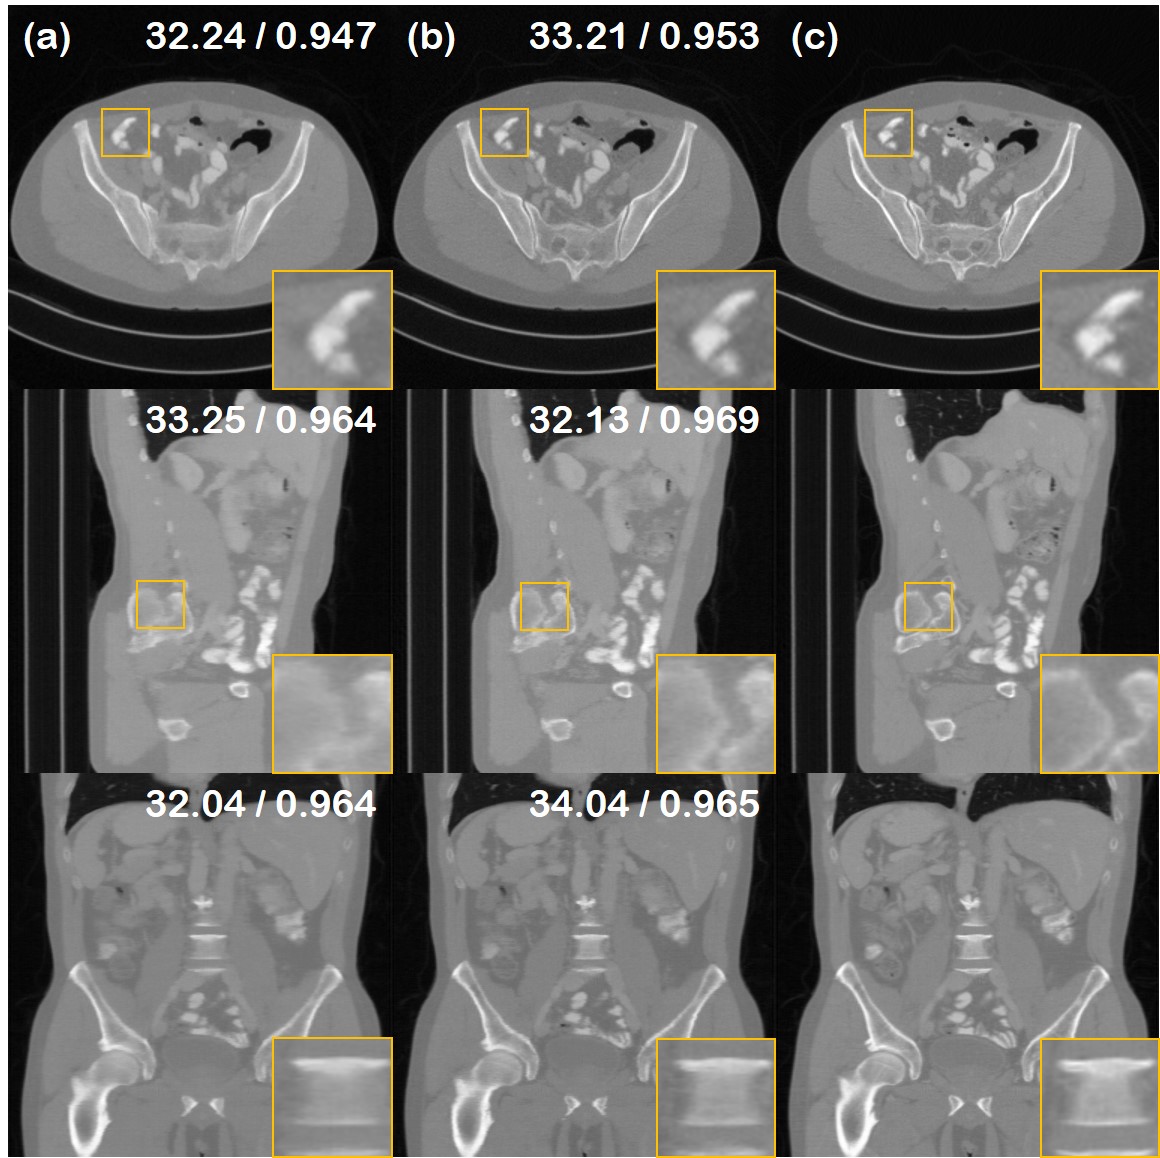

Refer to caption

Figure 10: Ablation study for the choice of augmented prior. (a) TV (xyz𝑥𝑦𝑧xyz) prior, (b) TV (z𝑧z) prior; proposed method, (c) Ground truth.